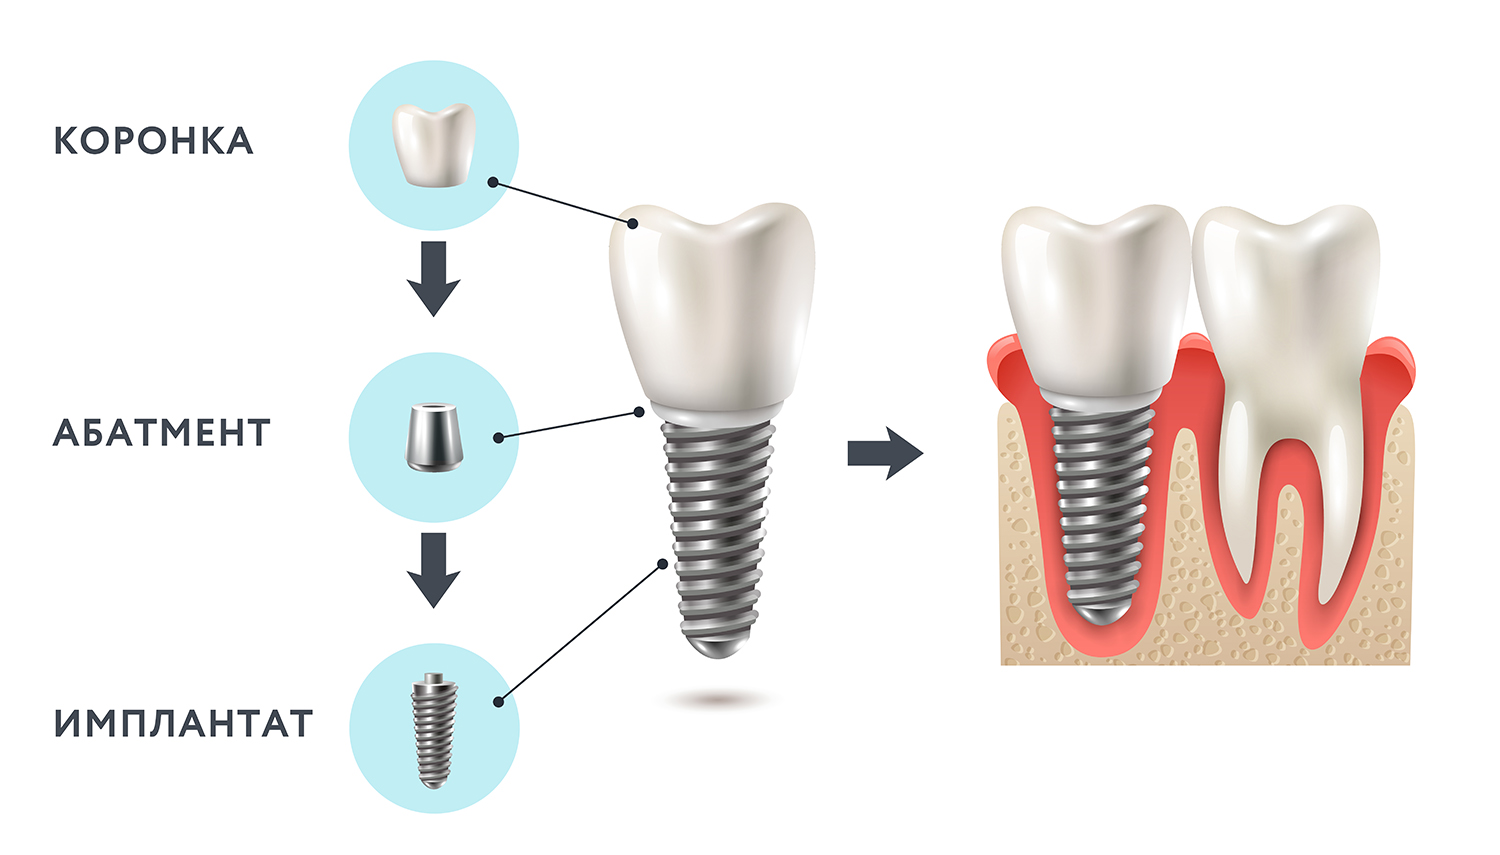

Рентген имплантов Alpha Bio: диагностика и качество